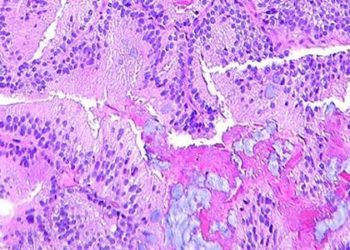

Study Rundown: Nasopharyngeal carcinoma (NPC) is routinely treated with radiation and chemotherapy, although these modalities are often associated with serious adverse events. Proton-beam radiotherapy is a newer technology which focuses radiation to the tumor site, minimizing effects on surrounding tissue. Intensity-modulated proton therapy (IMPT) uses multiple energy beams to better localize radiation and has been shown to reduce treatment-related side effects in the management of other head and neck cancers compared to intensity-modulated radiation therapy (IMRT). This retrospective cohort study sought to evaluate the oncologic effectiveness and safety profile of IMPT and IMRT in the treatment of nonmetastatic NPC. 77 patients being offered curative therapy for nonmetastatic NPC at a single center were included between 2016 and 2019. 36% of patients were treated with IMPT and 64% with IMRT. The median follow-up time was 30.3 months. In this time, there was no significant difference in overall survival or local-regional failure rates between the two groups. With respect to safety, 68% of patients in the IMPT group and 94% of patients in the IMRT group experienced adverse events rated Grade 2 or higher. These results demonstrate that, given its superior safety profile, IMPT may be a promising alternative to IMRT, which is the current gold standard of care, for the treatment of nonmetastatic NPC. The study provides support for expanding the role of IMPT for the safe treatment of head and neck cancers. Li et al’s study is primarily limited by its retrospective nature and relatively short follow-up time. This is particularly problematic as radiotherapy has been shown to cause significantly delayed adverse events. There were also some differences in baseline cancer and treatment-related characteristics between the two groups (see In Depth). A randomized controlled trial with several years of data may be appropriate to further substantiate the results described in this study.